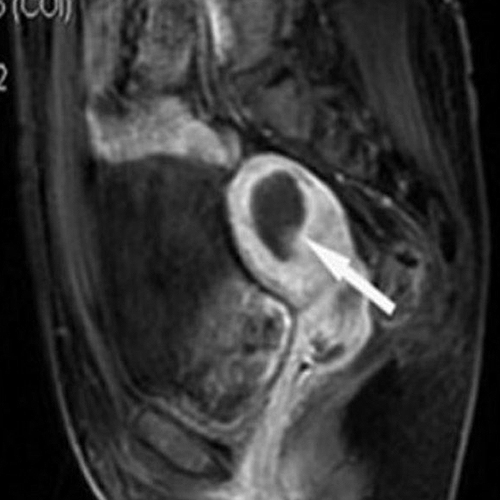

임신 준비중 발견된

9cm 거대 근종 진단

트리니티 내원

고주파용해술 시술 진행

치료 10개월 후

2cm로 부피 77% 감소